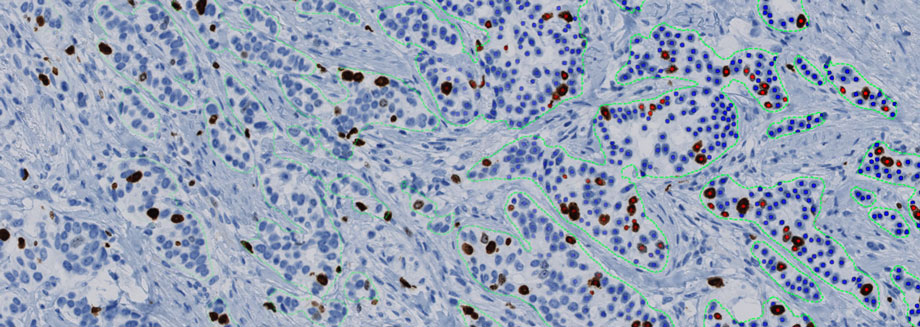

Targeted radionuclide therapy is a form of precision medicine where a radioactive substance is attached to a targeting moiety. It is administered through the body to specifically target cancer cells and irradiate them. The efficacy of these treatments can be determined by the level of radio-induced DNA damage that it causes. In one of the first cooperative projects Minerva and Visiopharm will develop quantitative AI-based image analysis to assess this level of DNA damage.

AI-driven image analysis

AI-driven precision pathology has the potential to play a crucial role in developing powerful new predictive assays. It provides a powerful tool for discovery of new biomarkers through the analysis of multiplexed image data, developing investigational devices for clinical trials, and developing scoring principles for novel tissue biomarkers. Moreover, it can aid in the development of image analysis for standardized and automated reading of increasingly complex biomarkers.